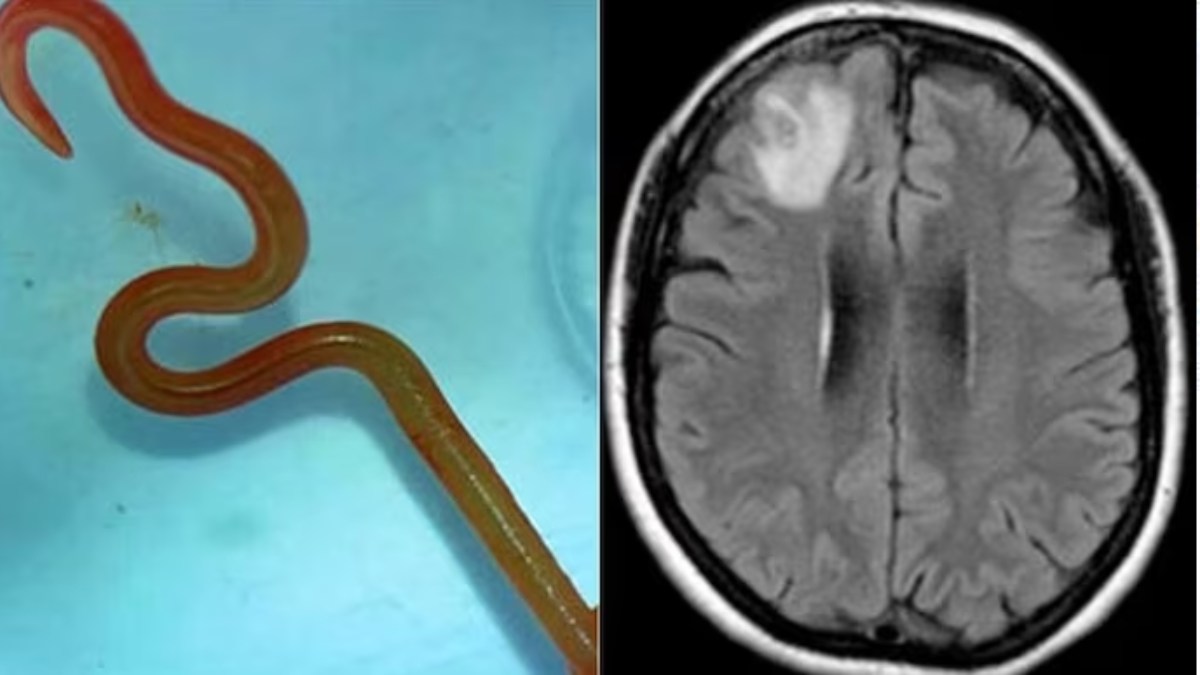

ಆಸ್ಟ್ರೇಲಿಯದಲ್ಲಿ ವಿಚಿತ್ರ ಘಟನೆಯೊಂದು ವೈದ್ಯ ಲೋಕವನ್ನೇ ಬೆಚ್ಚಿ ಬೀಳಿಸಿದೆ. ರೋಗಿಯ ಮೆದುಳಿನಲ್ಲಿ 8 ಸೆಂಟಿಮೀಟರ್ ಅಳತೆಯ ಜೀವಂತ ಹುಳವೊಂದು ಹರಿದಾಡುತ್ತಿರುವುದು ಕಂಡುಬಂದಿದೆ.

2022ರ ಹೊತ್ತಿಗೆ ಆಕೆಯ ರೋಗಲಕ್ಷಣಗಳು ಮರೆವು ಮತ್ತು ಖಿನ್ನತೆಯನ್ನು ಹೆಚ್ಚಿಸಿದವು. ಈ ವೇಳೆ ಇವರನ್ನು ಕ್ಯಾನ್ಬೆರಾ ಆಸ್ಪತ್ರೆಯಲ್ಲಿ ಮೆದುಳಿನ MRI ಸ್ಕ್ಯಾನ್ ಗೆ ಸೂಚಿಸಲಾಯಿತು. ಆದರೆ MRI ಸ್ಕ್ಯಾನ್ ವೀಕ್ಷಿಸಿದ ವೈದ್ಯರು ಧಂಗಾಗಿ ಹೋಗಿದ್ದಾರೆ. ಸ್ಕ್ಯಾನ್ ಪ್ರತಿಯಲ್ಲಿ ಮೆದುಳಿನಲ್ಲಿ ಯಾವುದೋ ಒಂದು ಸಣ್ಣ ಹುಳು ಇರುವುದು ಪತ್ತೆಯಾಗಿದೆ. ಅದು ಜೀವಂತವಾಗಿರುವುದನ್ನು ಕಂಡ ವೈದ್ಯರು ಗಾಬರಿಗೊಂಡಿದ್ದಾರೆ.

ಈ ಹುಳು ಒಫಿಡಾಸ್ಕರಿಸ್ ರಾಬರ್ಟ್ಸಿ ನೆಮಟೋಡ್ ಜಾತಿಗೆ ಸೇರಿದ ಮೂರನೇ ಹಂತದ ಲಾರ್ವಾ ಎಂದು ಗುರುತಿಸಲ್ಪಟ್ಟಿದೆ. ಈ ಪ್ರಕರಣ ವೈದ್ಯಕೀಯ ಇತಿಹಾಸದಲ್ಲಿ ಒಂದು ವಿಶಿಷ್ಟ ಘಟನೆಯಾಗಿದೆ. ಈ ಘಟನೆಯನ್ನು ಎಮರ್ಜಿಂಗ್ ಇನ್ಫೆಕ್ಷಿಯಸ್ ಡಿಸೀಸ್ ಜರ್ನಲ್ ನಲ್ಲಿ ದಾಖಲಿಸಲಾಗಿದೆ. ಸಾಮಾನ್ಯವಾಗಿ ಈ ಹುಳು ಆಸ್ಟ್ರೇಲಿಯಾದ ನ್ಯೂ ಸೌತ್ ವೇಲ್ಸ್ನ ಸ್ಥಳೀಯ ಕಾರ್ಪೆಟ್ ಹೆಬ್ಬಾವುಗಳ ಜಠರಗರುಳಿನ ವ್ಯವಸ್ಥೆಗಳಲ್ಲಿ ವಾಸಿಸುತ್ತದೆ.